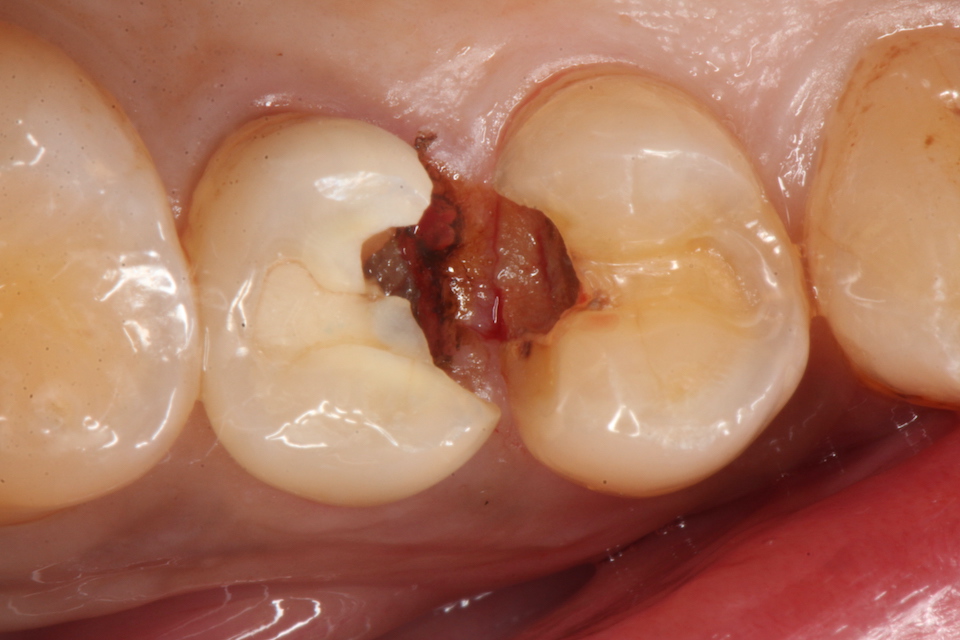

下顎7番の頬側歯茎部カリエスの原因 2025.06.04